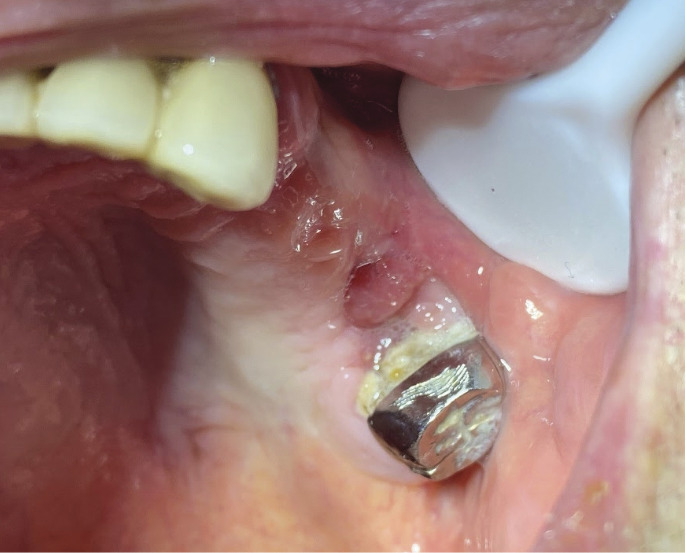

Le panoramique dentaire (fig. 1) met en évidence une solution de continuité de l’os alvéolaire au niveau de la dent 26 extraite. L’aspect est bourgeonnant (fig. 2). Un prélèvement histologique est effectué, qui montre une métaplasie malpighienne avec dysplasie de haut grade, sans infiltration du chorion, au niveau de la zone de jonction entre l’épithélium malpighien de surface et l’épithélium cylindrique cilié sinusien.